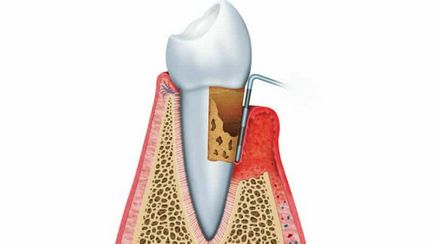

- resorbția parodontal. Procesul inflamator ajunge în locurile în care dintele este aliniat cu osul. Periodontal - țesut conjunctiv, constând dintr-un ligament mic, care ajută dintele este stabil atașat la osul maxilar. Inflamația cauzează distrugerea ligamentelor și a osului, care promovează apariția așa-numitului „buzunar parodontale“ (imaginea de mai jos). Ele reprezintă vidul corespunzător volumului de spațiu parodontale distruse și fixarea-l la os deteriorat. Aceste goluri sunt umplute cu un tesut activ de inlocuire, germeni, fluide patologice si puroi.

Determinarea adâncimii pungilor

Tratamentul chirurgical în acest caz, se va curăța canalele și țesutului de granulație, contribuind la îmbunătățirea sănătății.